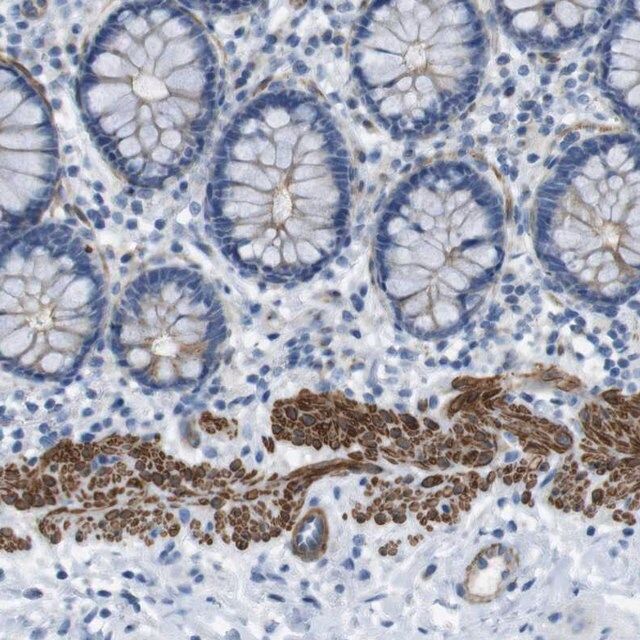

YIF1A (Yip1 interacting factor homolog A) belongs to the Yip1p/Yif1p family of proteins, which in humans, contains nine members. YIF1A is the human ortholog of Yif1p, which is a budding yeast protein. It resides in endoplasmic reticulum (ER), ER-Golgi intermediate compartment (ERGIC) and steady state cis-Golgi. This protein has four-five putative transmembrane regions, present at the C-terminal. The molecular weight of this protein is 35.5kDa, and it has a hydrophilic N-terminal, facing the cytoplasm.

YIF1A (Yip1 interacting factor homolog A) is a Yip1p interacting protein, with which it forms a heteromeric complex. This complex is essential for the binding of endoplasmic reticulum (ER)-derived vesicles with Bos1p and Sec22p proteins of SNARE complex. It might be involved in maintaining the structure of Golgi apparatus. It is also an interacting partner of vesicle-associated membrane protein (VAMP) associated protein B (VAPB), which is an essential part of the early secretory pathway. Both these proteins play essential roles in ER-Golgi transport, and errors in YIF1A sorting might be a contributing factor to VAPB-associated motor neuron disease. It is also essential for the normal growth of dendrites. It has a ubiquitous expression in the central nervous system (CNS). Studies in mice show that this protein could be one of the factors implicated in amyotrophic lateral sclerosis (ALS).

- IHC tissue array of 44 normal human tissues and 20 of the most common cancer type tissues.